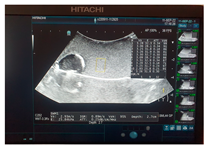

| Ultrasound | ![]() | ![]() | ![]() |